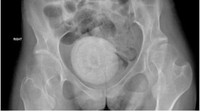

Jurnal Urology Case Reports mempublikasi kasus yang terjadi pada wanita muda berusia 27 tahun. Ia mengeluhkan sulit menahan buang air kecil, penurunan nafsu makan, muntah, hingga sakit perut yang parah. Setelah diperiksa, ternyata ada batu seukuran jeruk besar di antara organ panggulnya. Batu vagina yang bersarang di antara organ panggulnya itu sangat besar, sehingga menekan kandung kemihnya. (Foto: Jurnal Urology Case Reports).